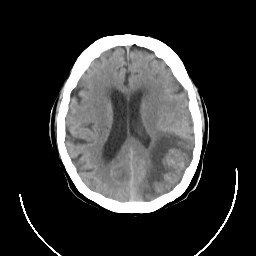

CT Study #3 -- Slice #17

Tour 1: Next/Previous/Start: This large cerebral infarct occurred in the setting of atrial fibrillation and caused a dense fluent aphasia. The CT scan shown here was obtained 5 days after the onset of stroke symptoms. View the temporal movie of this slice to see the evolution of the lesion over the 5 day period. Significant swelling in the infarcted area produces obvious shift of the midline by day 5. This corresponded clinically to a diminished level of arousal, which resolved after 2 days.